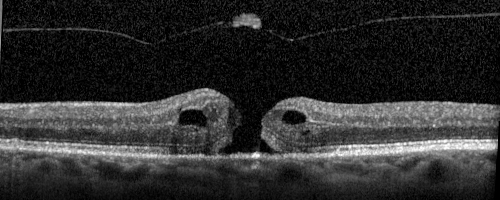

Stage II Macular Hole - PPV without ILM peel

77 year old man with 20/40 VA on presentation. Macular hole did not abort and vision dropped to 20/63. Post PPV vision was 20/25 within 6 months